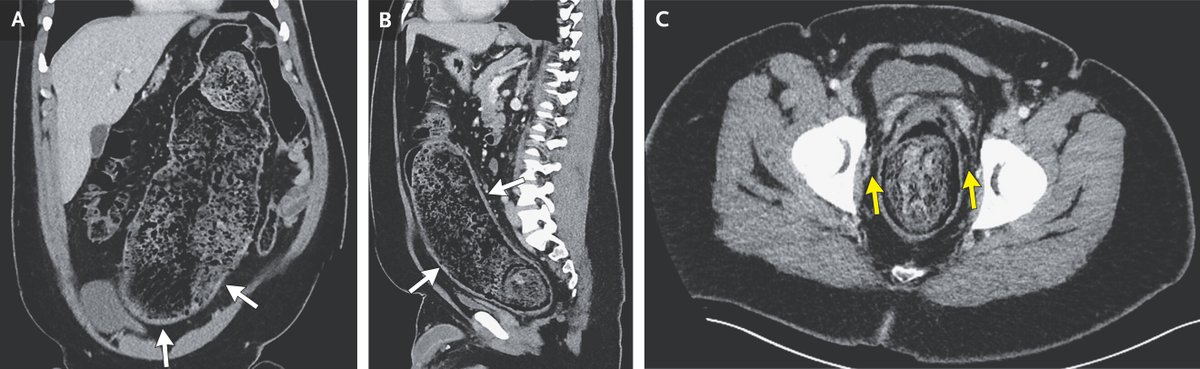

A 30 y/o man with a 15-month history of intermittent discomfort in the right upper quadrant of the abdomen. The physical examination revealed hepatomegaly with a palpable hepatic mass. - What is the diagnosis ? #medtwitter #foamed #usmle

22